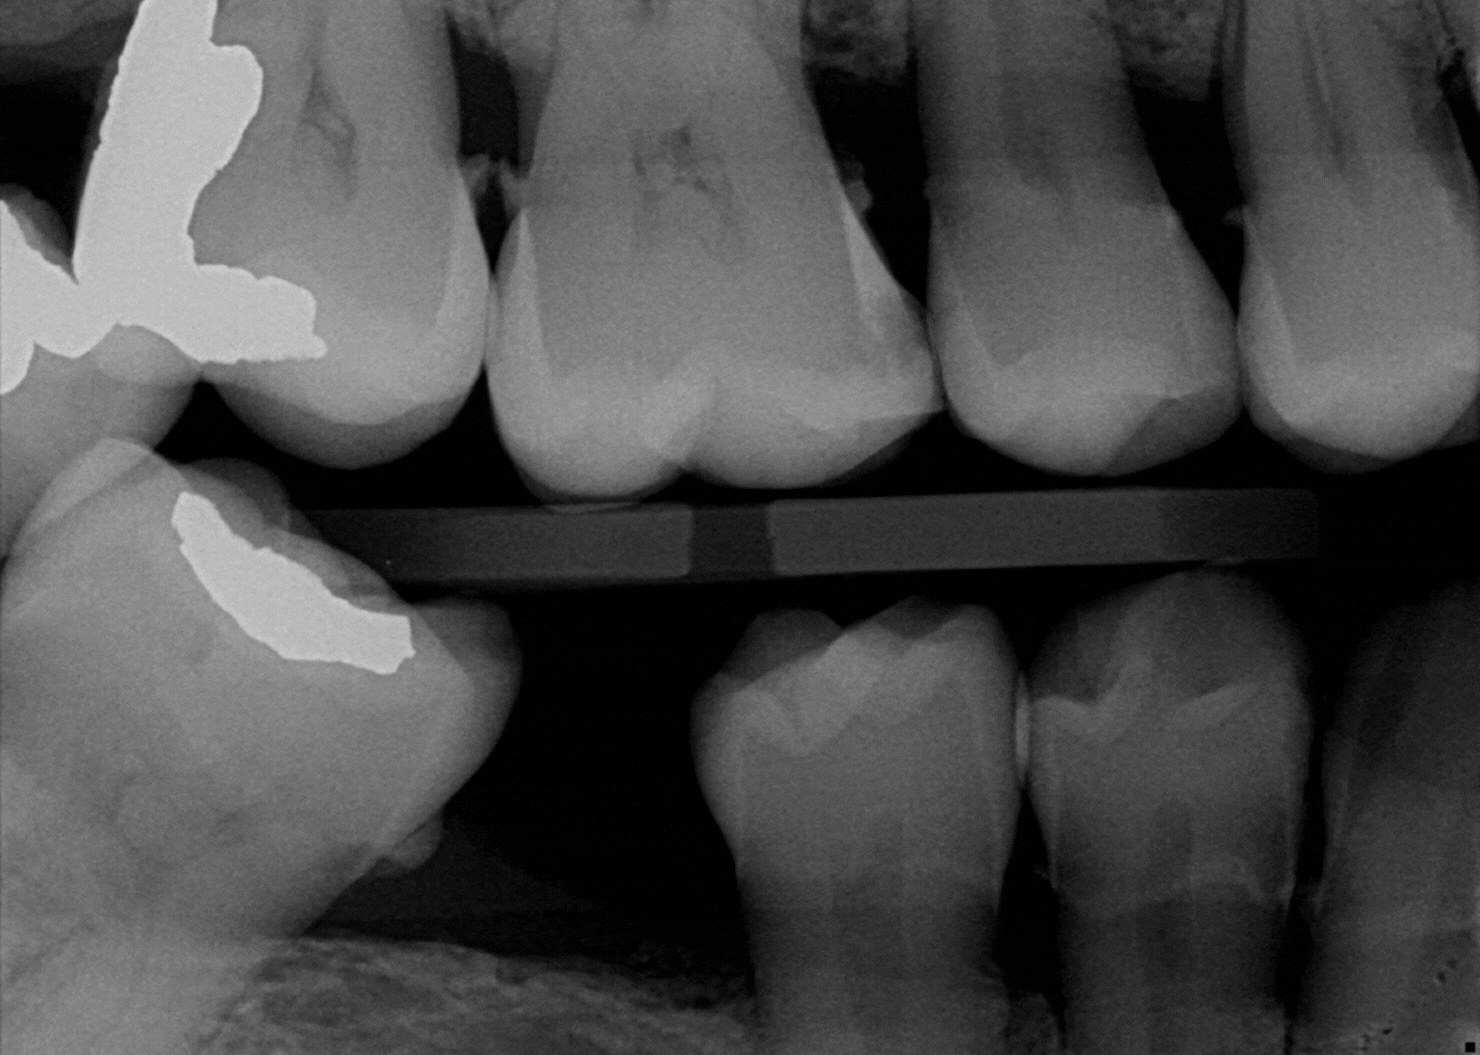

Trained on millions of real cases, Overjet is the only technology cleared by the FDA to detect, outline, and

quantify oral pathologies, down to a fraction of a millimetre.

Overjet's AI detects and highlights pathologies, anatomical structures, and prior restorations.

Overjet can automatically detect and quantify interproximal caries, bone level measurements for periodontal assessment, and calculus deposits. It also highlights areas of concern in a clear, visual format to support clinical decision-making.

Yes. Overjet is compatible with bitewings, periapicals, and panoramic radiographs, offering multi-view support to assist in a range of diagnostic workflows.